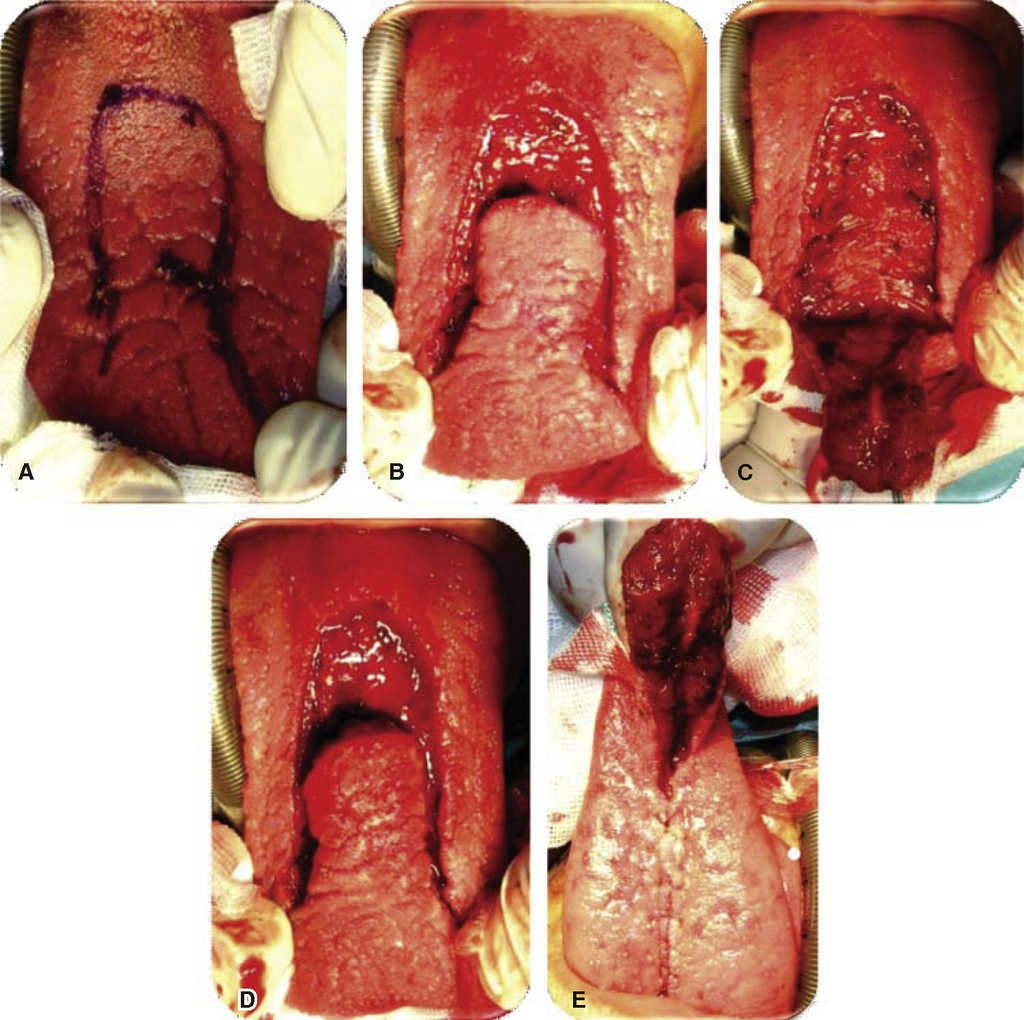

Se programa para cierre de fístula oronasal con colgajo a distancia de lengua de base anterior. Bajo anestesia general, con intubación nasotraqueal, se infiltra el paladar y el sitio donante con lidocaína con epinefrina al 2% y 1:100,000 con fines hemostáticos, se coloca un abreboca tipo Digman y se realiza una incisión perifistular con hoja de bisturí No. 15 y electro bisturí, se realiza disección de los bordes del defecto evertiéndolos y suturándolos con poliglactina 910 de 4-0, logrando un cierre del 100% del plano de la mucosa nasal, se realiza irrigación con solución fisiológica por vía nasal observado la nula salida de líquido por el defecto ya cerrado; se retira el abreboca tipo Digman y se coloca un abreboca de Mackinson, se tracciona la lengua con un punto de sutura de seda 2-0 en la punta para presentarla, se realiza un diseño de colgajo de lengua de base anterior 20% mayor al tamaño del defecto, y de una longitud aproximada de 5 cm asegurándose que cubriera la totalidad del defecto evitando la tensión; se realiza hemostasia con electro cauterio y con sutura de poliglactina 910, se realiza sutura del sitio donante en dos planos con poliglactina 910 4-0 verificando la ausencia de hematomas; se rota el colgajo de lengua sobre el defecto y se sutura con puntos simples de poliglactina 910 sobre los bordes del defecto. Se termina el acto quirúrgico sin complicaciones ni accidentes (Figuras 2,3, 4). En este caso no se colocó fijación intermaxilar, ya que por la edad del paciente se considera que es cooperador.

Figura 2 A. Diseño de la incisión perifistular. B. Incisión perifistular con electro bisturí. C. Disección mucosa nasal, rotación del tejido. D. Sutura y cierre del plano nasal.

Figura 3 A. Diseño del colgajo de lengua de base anterior. B. Incisión con hoja de bisturí #15. C. Disección colgajo de 7mm espesor incluyendo mucosa y músculo. D. Colgajo ya disecado. E. Sutura de lecho donador.